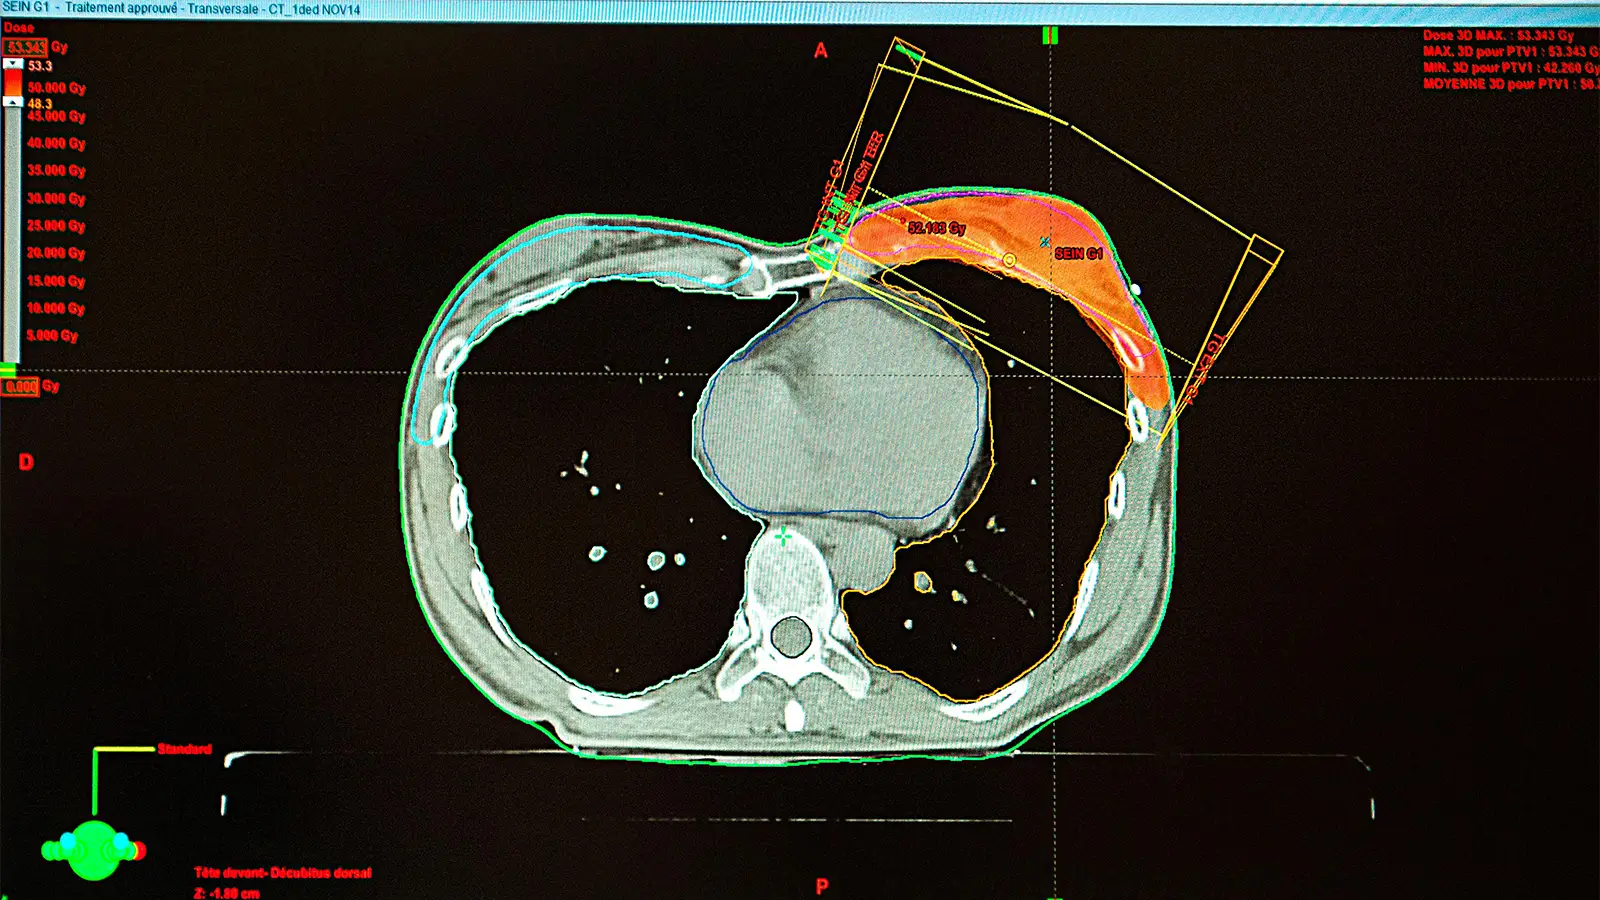

Contemporary external beam radiation therapy (EBRT) techniques appear to have reduced the risk of cardiovascular disease (CVD) among women with left-sided breast cancer, a large retrospective cohort study suggested.

Breast radiotherapy techniques used before the 1980s exposed surrounding organs to large doses of radiation, so women with left-sided tumors historically received higher mean heart doses than women with right-sided tumors, which increased their risk of coronary artery disease, cardiomyopathy, valvulopathy, arrhythmias, and pericardial disease.

The findings in this study “provide population-level reassurance that modern radiation techniques have largely mitigated the excess long-term cardiovascular mortality and morbidity historically associated with left-sided [breast cancer] treatment for women with typical radiation exposure,” Abdel-Qadir and colleagues noted.

“For patients with low baseline CVD risk and low anticipated cardiac exposure, the incremental absolute risk from contemporary radiotherapy may be very small, often outweighed by oncologic benefit,” Guha wrote. “For patients with high baseline risk or higher expected cardiac exposure, the same relative effect can translate into a larger absolute excess risk, making cardiac-sparing imperative.”